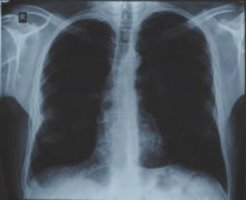

![]() Рис. 4 |

И вот ровно через год после первого снимка контрольный снимок показал абсолютно здоровые легкие, без каких бы то ни было следов перенесенной болезни (рис. 4).